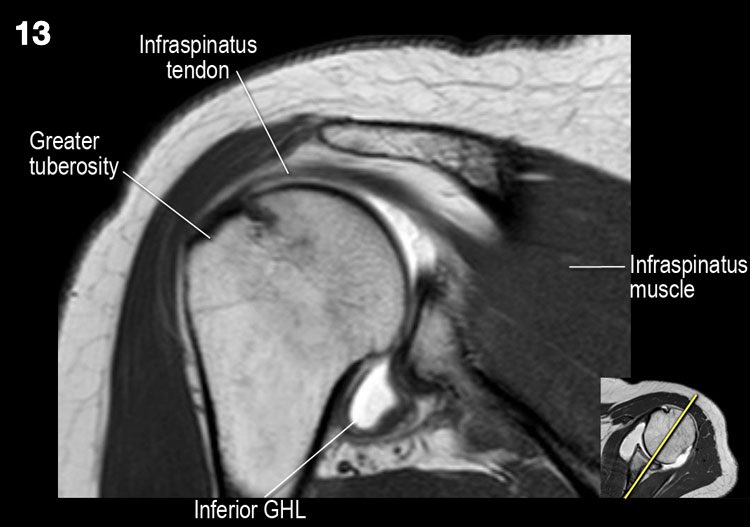

Hình ảnh mặt sau

Hình ảnh thể hiện các cơ và gân của cơ trên gai, cơ dưới gai và cơ tròn bé. Tất cả đều bám vào mấu động lớn.

Giải phẫu mặt cắt đứng dọc và danh sách kiểm tra

- Lưu ý các cơ chóp xoay và tìm kiếm dấu hiệu teo cơ.

- Tìm kiếm rách gân cơ dưới gai.